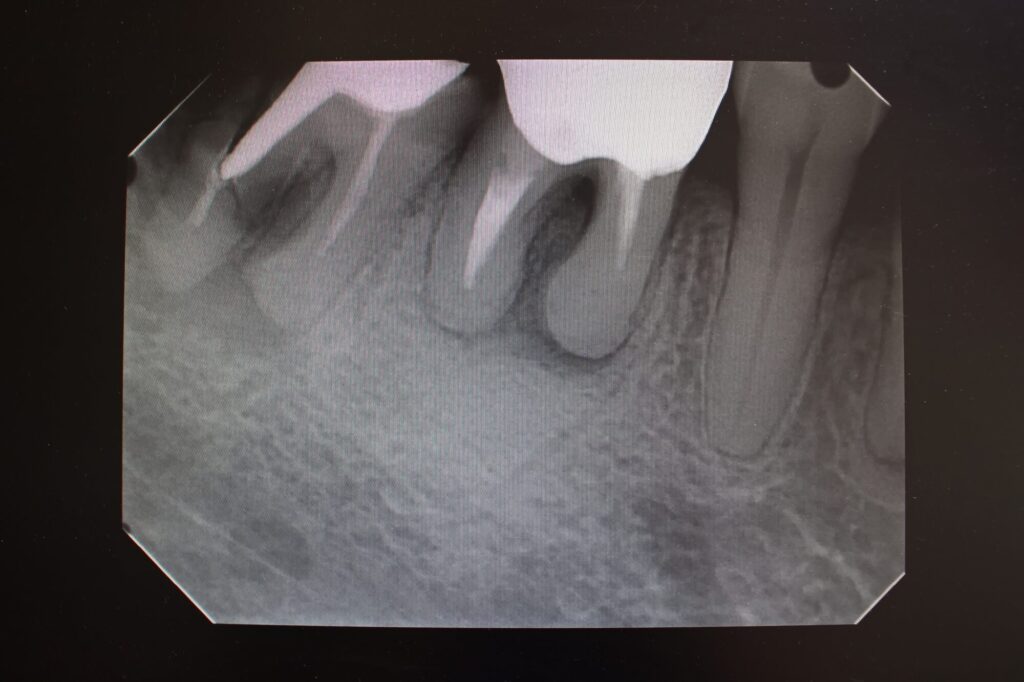

虫歯を早期に発見できれば、抜髄のように歯の強度を下げる治療をしなくて済むため、歯根破折のリスクを下げられるでしょう。また、レントゲンやCT検査によって、肉眼では確認できない初期段階の歯根破折も早期に見つけられます。